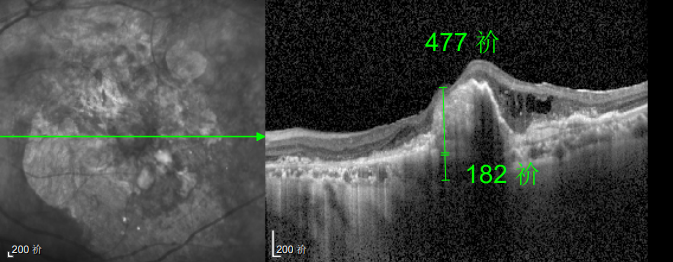

△規(guī)劃化治療后的左眼

這次教訓讓林婆婆徹底醒悟,此后她嚴格遵照王曉波主任的醫(yī)囑,定期隨訪、規(guī)范治療,再也不敢有絲毫懈怠。雖然左眼視力最終僅恢復至0.3,但穩(wěn)定的視力狀態(tài)讓她格外珍惜。